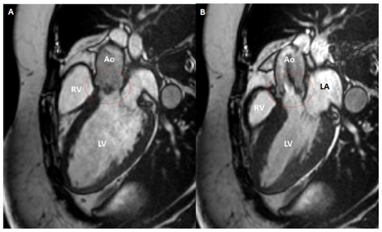

NBTE-nin qiymətləndirilməsində ürək MRT-nin rolu yaxşı qurulmamışdır. Ürəyin MRT-si kardiak KT ilə müqayisədə daha aşağı məkan rezolyusiyasına malikdir və exokardioqrafiya ilə müqayisədə aşağı temporal rezolyusiyaya malikdir. Bununla belə, ürəyin MRT-si NBTE olan xəstələrdə regurgitant volumların dəqiq kəmiyyətini müəyyən etməyə və kontrastlı, T1/T2 görüntülərii toxumaların xarakterizasiyasına imkan verir.

Şəkillər